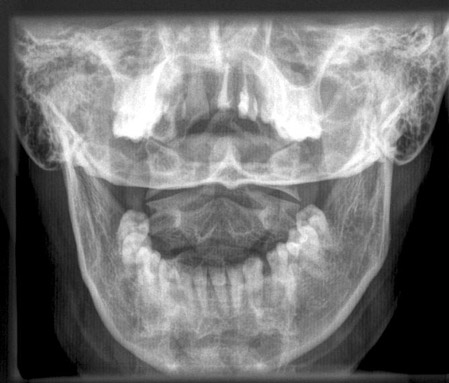

Dens a.p.

Fehler

Überlagerung des Atlas und der Densspitze durch die Hinterhauptschuppe. Die Bissfläche der Zähne des Oberkiefers bilden sich weit oberhalb der Densspitze ab.

Abhilfe

Kinn geringfügig stärker gegen den Hals anziehen lassen.